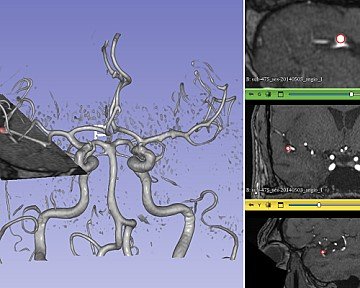

Anévrisme détecté automatiquement par notre algorithme dans un volume d'IRM angiographique. À gauche : vue 3D ; bandeau de droite: 3 coupes dans le volume IRM.

Erwan Kerrien : Le défi tient au fait que les anévrismes sont de très petites structures, en moyenne de 5 à 8 mm de diamètre, de localisation variable. Pour les détecter, il faut non seulement disposer d’images de qualité suffisante mais également être capable d’interpréter celles-ci, ce qui dépend du niveau d’expertise de la ou du radiologue, des moyens d’analyse dont il dispose ou encore de son état de fatigue. L’idée était donc d’élaborer un outil qui utilise les techniques d’intelligence artificielle pour accompagner la praticienne ou le praticien dans son diagnostic en détectant automatiquement les anévrismes. L’algorithme lui-même repose sur une architecture de réseau de neurones profonds développée par Youssef Assis, un doctorant que nous encadrons depuis 2020 et qui a soutenu, cette année, sa thèse cofinancée par le CHRU de Nancy et la région Grand Est, dans le cadre du plan de financement doctoral de l’ANR. Il s’agit ensuite de valider l’efficacité de l’outil informatique. C’est ce que fait Liang Liao, un second doctorant, également praticien hospitalier, qui a intégré le projet en 2021. Le but est d’évaluer les performances des expertes et experts par rapport à celles des non-expertes et non-experts, et de déterminer comment l’IA, à travers l’algorithme développé, peut améliorer ces dernières. Selon nos premiers résultats, un non-expert présente un taux de sensibilité moyen de 75%, c’est-à-dire qu’il détecte 3 anévrismes sur 4, tandis que celui d’un expert est de 84% à 90% selon qu’il réalise une analyse rapide ou poussée. Avec la détection automatique, le taux de base est de 86%. Dans tous les cas, l’IA permet donc de renforcer les performances en matière de détection.